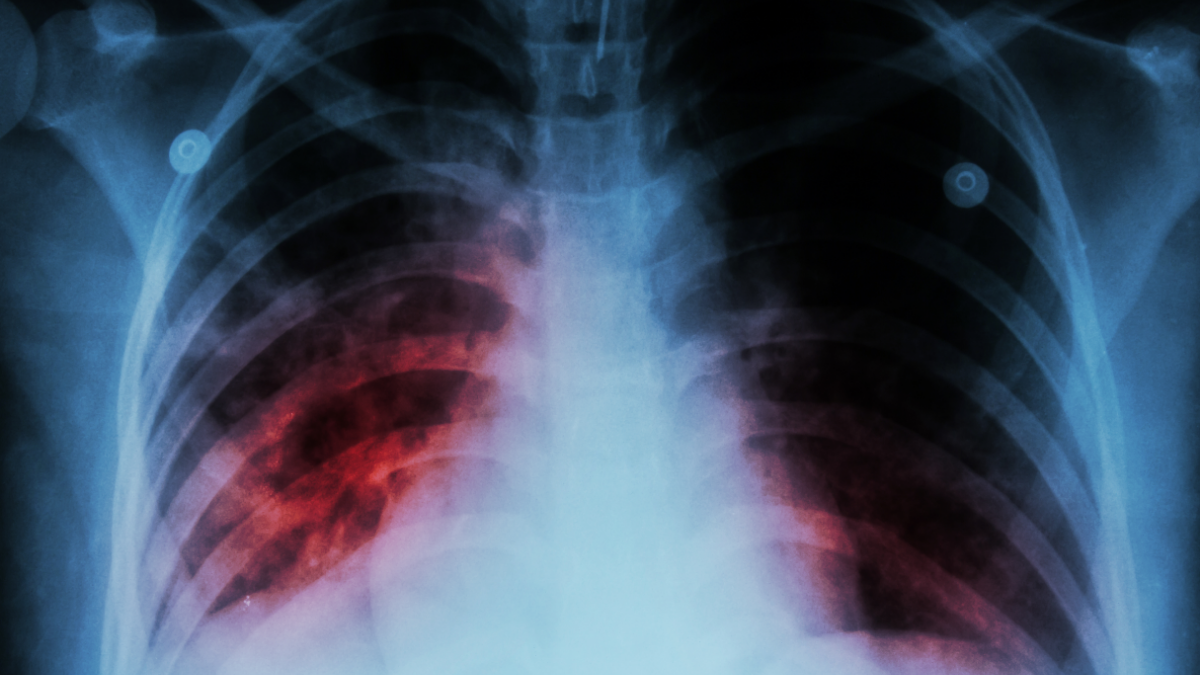

Last year, 198 children and adolescents contracted tuberculosis.

“Elchi” reports that this was stated by Irada Akhundova, director of the Scientific Research Institute of Lung Diseases of the Ministry of Health.

She stated that this indicator for 2024 was 278.

“While the incidence rate of tuberculosis per 100,000 people was 41.1 in 2015, this figure decreased to 21.5 in 2025. Approximately two-thirds of tuberculosis patients are men, and one-third are women. The detection level of the disease has also significantly increased. For instance, while this indicator was 53 percent in 2015, it reached 86 percent in 2025,” she said.